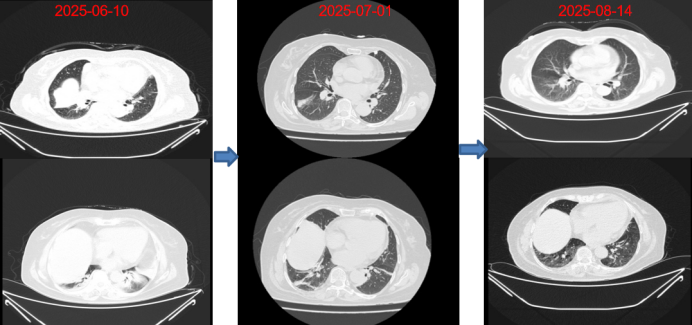

7月14日,动态胸片示双侧膈肌移动度正常。平静呼吸时,右侧膈肌移动度为12.0 mm,左侧为16.0 mm(图8);尽力呼吸时,右侧膈肌移动度为48.0 mm,左侧为50.0 mm(图9)

8月14日复查胸部CT:病变较前明显吸收改善(图10)

图片

8  平静呼吸时动态胸片(2025-07-14)

9  尽力呼吸时动态胸片(2025-07-14)

10  胸部CT对比图片

注:膈肌抬高、双下肺不张逐步好转。